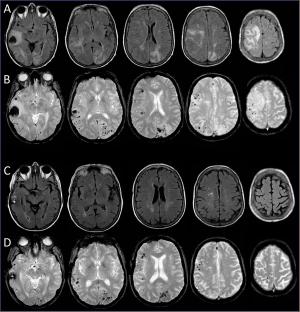

A 71-year-old woman presented to the emergency department with subacute headaches and altered behavior that was initially attributed to emotional distress. What did the tests show?